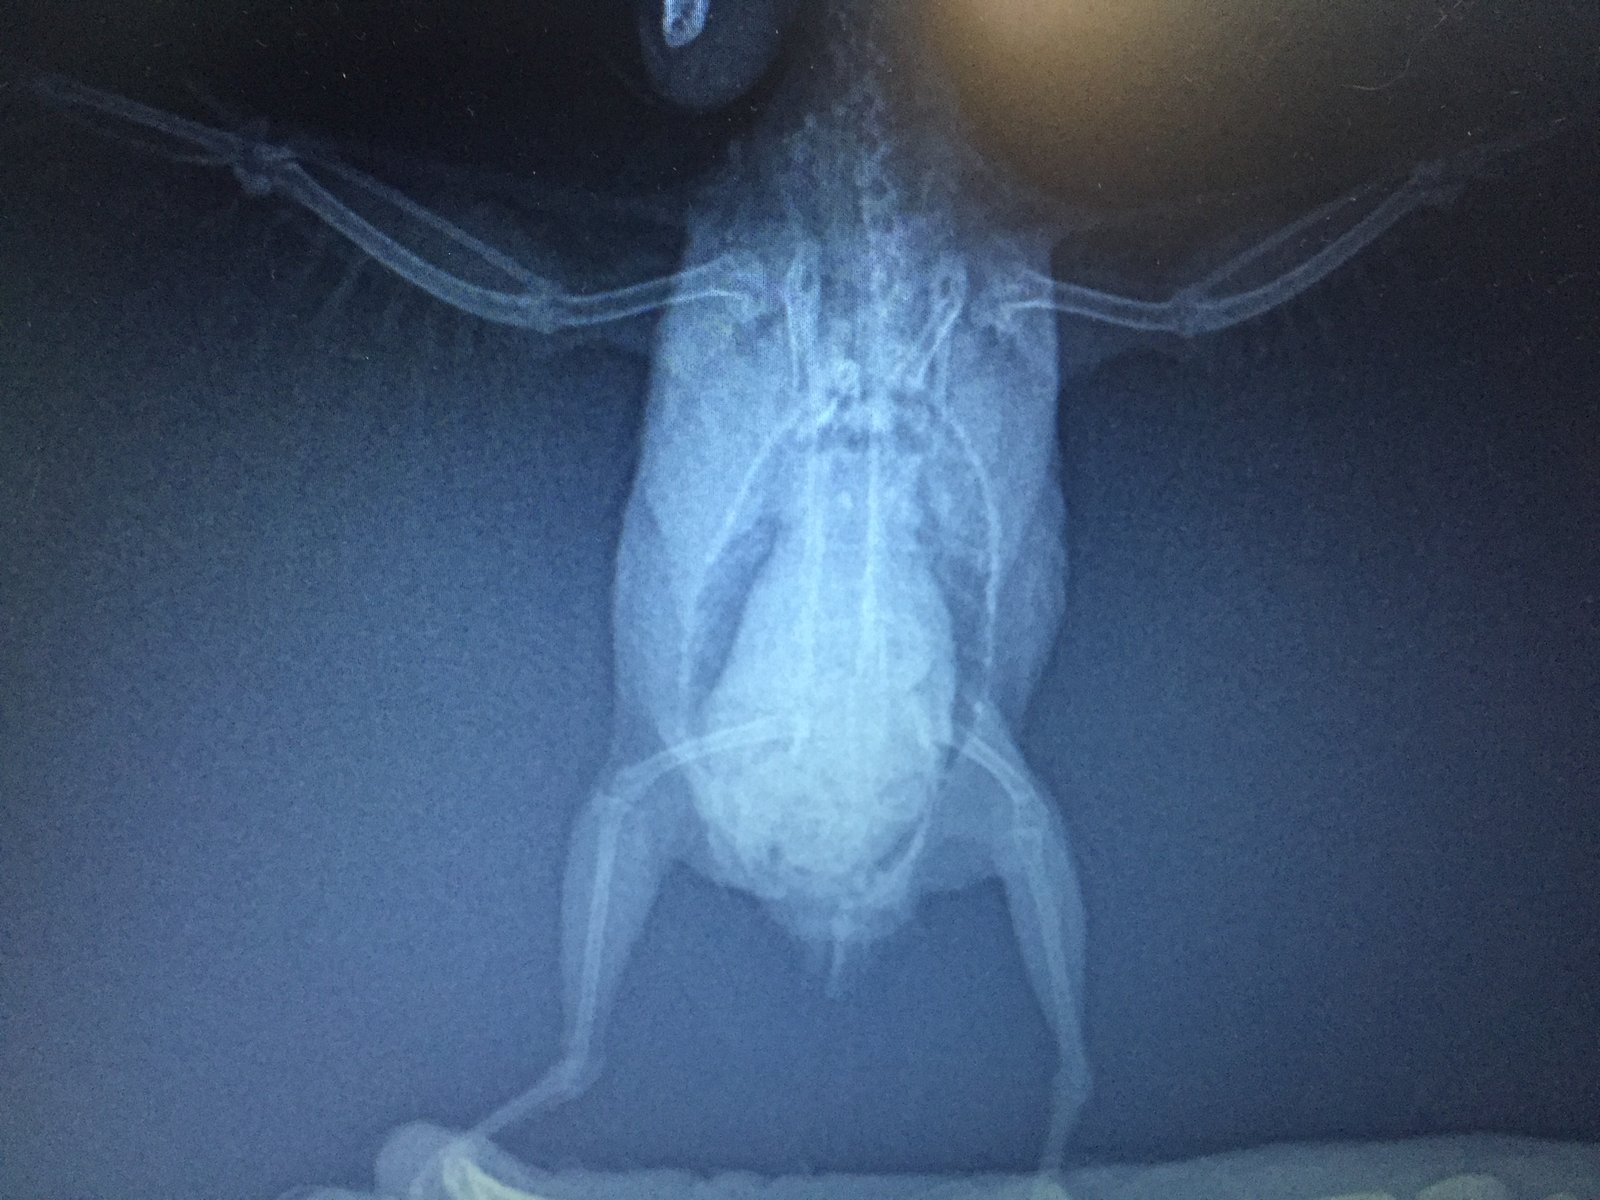

Сделали рентген и анализ помета.

По рентгену (см. приложение) – увеличен живот, печень.

Повторный рентген врач сказала можно сделать, но искать и определять у какого органа опухоль нет смысла, так как на лечение это не повлияет.

Фотографии сегодня сделала, насколько смогла четкие, трогать боюсь, он пищит, вырывается, посмотрите пожалуйста, фото рентгена от 05.06 прилагаю. Что это за опухоль? Чего ждать? Какая должна быть диета? Я сегодня где-то в ветке прочла, что морковь нельзя, а она у нас самая любимая. Из клетки не входит, со мной не общается. Я боюсь вытаскивать его в таком состоянии. Нужно ли его вытаскивать и провоцировать полеты? Как помочь?